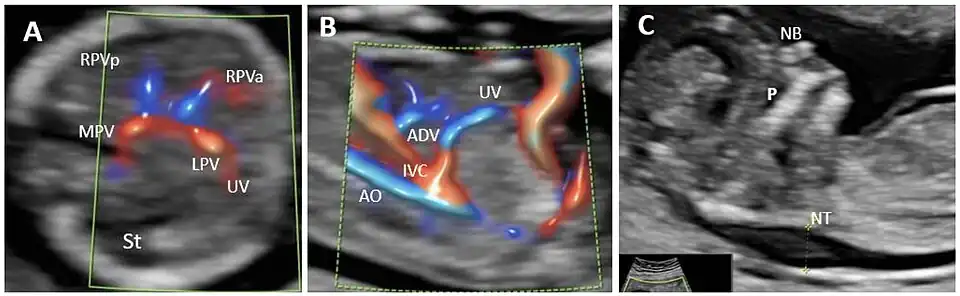

In the fetus, the ductus venosus ("DV"; Arantius' duct after Julius Caesar Aranzi[1]) shunts a portion of umbilical vein blood flow directly to the inferior vena cava.[2] Thus, it allows oxygenated blood from the placenta to bypass the liver. Compared to the 50% shunting of umbilical blood through the ductus venosus found in animal experiments, the degree of shunting in the human fetus under physiological conditions is considerably less, 30% at 20 weeks, which decreases to 18% at 32 weeks, suggesting a higher priority of the fetal liver than previously realized.[3] In conjunction with the other fetal shunts, the foramen ovale and ductus arteriosus, it plays a critical role in preferentially shunting oxygenated blood to the fetal brain. It is a part of fetal circulation.

The pathway of fetal umbilical venous flow is

umbilical vein left portal vein ductus venosus inferior vena cava eventually right atrium.

This anatomic course is important to recall when assessing the success of neonatal umbilical venous catheterization, as failure to cannulate through the ductus venosus results in malpositioned hepatic catheterization via the left or right portal veins. Complications of such positioning can include hepatic hematoma or abscess.